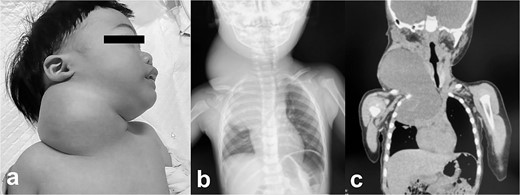

Pathologic findings on the first administration. The tumor size in the cervical region was quite large and there may be a risk of airway system compression. (a) physical finding, (b) chest X-ray, (c) plain computed tomography.

A male infant weighing 2726 g was born at 38 weeks of gestation. Antepartum ultrasonography and magnetic resonance imaging (MRI) revealed a right cervical cyst, suggestive of a lymphangioma. A right cervical cyst was noted at birth and gradually decreased in size thereafter. However, right cervical swelling became evident when he cried (Fig. 1a and b). An MRI obtained at 21 months of age showed a huge cyst in the right cervical mediastinal region. Following diagnosis of a lymphangioma with hemorrhage, he was treated with Eppikajutsuto®, a Japanese traditional Kampo medication, 2 g/d (0.2 g/kg). An MRI revealed tumor enlargement after oral administration of Eppikajutsuto® for 2 months. A complex vascular malformation was noted (Fig. 2) and the dose was increased to 5 g/day (0.5 g/kg). A repeat MRI 2 months after the dose increase showed no reduction in the size of the tumor. After another 4 months, the dose of Eppikajutsuto® was further increased to 7.5 g/d (0.65 g/kg). The tumor in the cervical region had enlarged further with an accompanying risk of airway system compression (Fig. 3a–c). A puncture and suction of the lymphangioma was performed for volume reduction and the content was prepared for bacterial culture. The content was dark red in color, which was consistent with hemorrhage. The white blood cell count (WBC) was 19 190/μl and the C-reactive protein (CRP) concentration was 5.77 mg/dl. He was admitted to the hospital to undergo treatment with intravenous and oral antibiotics. The bacterial culture results were negative. On the 22nd day of hospitalization, the WBC count was 8780/μl and the CRP concentration was 0.39 mg/dl. On the 24th day of hospitalization, a Denver shunt was inserted from the right cervical region to the abdominal cavity to reduce the volume of the cervical cyst to prevent airway obstruction (Fig. 4a–c). A pump chamber with a backflow prevention valve was implanted in the right anterior chest subcutaneous tissue (Fig. 4b). By applying pressure to the chamber, the cyst fluid in the neck was returned to the abdominal cavity. The patient was discharged on the 6th post-operative day. The swelling in the right neck was reduced and the pressure on the trachea was relieved based on the X-ray findings (Fig. 4c and d). On the 5th day after hospital discharge, the patient was febrile and the right neck swelling recurred. A hemogram revealed severe anemia and bleeding within the neck cyst was suspected. He was readmitted to the hospital and on the 2nd day after admission the cervical cyst was punctured, which yielded bloody contents. A transfusion was performed for anemia secondary to hemorrhage in the neck cyst. Sirolimus (1 mg), a mammalian target of rapamycin inhibitor, was added 7 months after starting Eppikajutsuto® due to a concern that administration of a Kampo medication and insertion of the Denver shunt might not be effective. An X-ray showed that the tip of the catheter may have moved within the cyst, which caused the catheter tip to penetrate the cyst and resulted in bleeding within the neck cyst (Fig. 5a). Serial MRI findings showed that the old bleeding site was within the mediastinal region of the lymphangioma. Revision surgery was performed 3 weeks after inserting the Denver shunt. Intraoperative findings showed that the tip of the catheter had penetrated the cyst wall (Fig. 5c). There were cyst walls with a septum on the mediastinal side of the cyst and when incised old bleeding was noted and the walls were opened as much as possible (Fig. 5d). The tip of the catheter was rounded and fixed with threads. The catheter was returned to the cyst and the wound was closed (Fig. 5b). The patient was discharged 9 days after the 2nd surgery. The concentration of sirolimus on the 14th day of administration was 9.9 ng/mL (normal range: 5–15 ng/ml). On the 16th day after the second hospital discharge, the neck had enlarged, the surgical wound was erythematous, and discharge was noted at the site of the pump chamber. Bacterial cultures of the punctured the neck cyst content and the wound discharge grew Staphylococcus aureus. On the 24th day after the 2nd hospital discharge, the blood concentration of sirolimus 1 month after starting oral administration was 19.7 ng/ml. Therefore, the oral administration of sirolimus was temporarily discontinued. At the same time the patient developed a high fever and the 3rd operation was performed to remove the Denver shunt due to a catheter infection. The blood concentration of sirolimus 6 days after discontinuation was 1.4 ng/ml. An MRI on the 6th post-operative day from the 3rd operation revealed two different intensities in the neck and mediastinal regions where the Denver shunt was inserted (Fig. 6a). On the 10th day after the 3rd operation, the patient was discharged from the hospital but laboratory testing showed an elevated WBC count (13 250/μl) and CRP concentration (6.03 mg/dl). Three months after the 3rd hospital discharge, the right neck swelling abruptly decreased in size and the WBC count and the CRP concentration decreased to the normal range. An MRI 2 months after the 3rd operation showed that the mediastinal lesion was smaller with near-complete regression (Fig. 6b). The neck swelling was minimal 6 months after the 3rd operation. An X-ray showed no tumor shadow and no compression of the trachea by the lymphangioma (Fig. 6c) and magnetic resonance angiography (MRA) showed that the lymphangioma had regressed (Fig. 6d). Currently, no right cervical swelling is evident when the patient cries (Fig. 6e and f) and he is doing well with oral administration of Eppikajutsuto® (7.5 g/d [0.65 g/kg]).